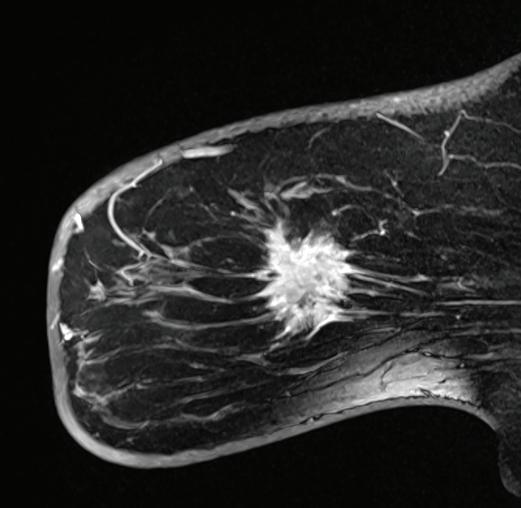

Your doctor says you should have a breast MRI and/or an MRI-guided breast biopsy. Both involve MRI, or magnetic resonance imaging, a technology that uses a magnetic field and pulses of radio wave energy to make detailed, high-quality images.

How are these procedures different and how can they help? Amanda Feibusch, MD, a radiologist at the Jacqueline M. Wilentz Comprehensive Breast Center at Monmouth Medical Center Southern Campus, explains.

What is a breast MRI?

A breast MRI is a test performed most commonly as a high-risk screening in addition to an annual mammogram. The breast MRI helps with problem-

solving following diagnostic imaging or with evaluating the extent of disease following a cancer diagnosis.

Intravenous contrast is required for a breast MRI. This entails administering a special dye that makes it easier for healthcare providers to see differences or abnormalities in the body. If an abnormality is detected on a breast MRI, the radiologist analyzing the images will recommend an MRIguided biopsy. This will determine if the abnormality is benign (noncancerous) or malignant (cancerous).

What is an MRI-guided breast biopsy?

An MRI-guided breast biopsy is a minimally invasive procedure performed to take a sample of the tissue in question. This sample can be used to evaluate a suspicious finding seen on a breast MRI and potentially diagnose cancer. The procedure usually takes about an hour.

What happens during the biopsy?

We take a series of images, and the radiologist locates the area in question. We inject a local anesthetic for comfort, make a very small nick in the skin and take a few samples of tissue. The actual tissue sampling only takes a few minutes. Tissue samples are sent to the pathology lab for analysis. A tiny marker is then placed in the sampled area to provide a reference point if surgical intervention is required following the tissue diagnosis, which is obtained within a couple of days.

What’s the biggest benefit?

Early detection saves lives. MRIguided breast biopsy provides a minimally invasive way to sample suspicious tissue in the breast. It allows pathologic diagnosis that will provide important information for a surgeon if surgical management is subsequently recommended.